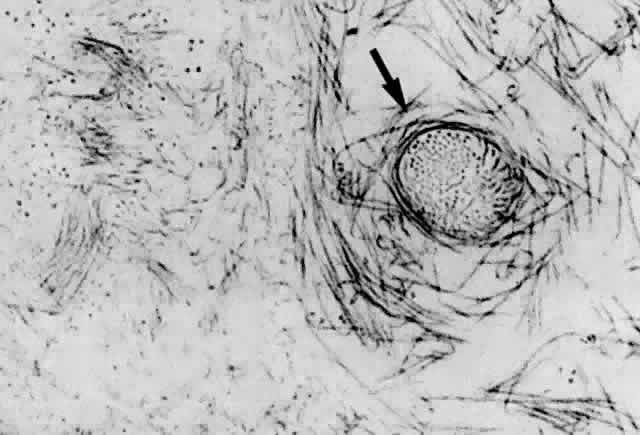

Ultrastructural studies90 have demonstrated that collagen organized in bundles of packed, parallel fibrils (Fig. 7) is the only microscopic structure that could correspond to these fibers. It has been hypothesized that the visible vitreous fibers form when HA molecules no longer separate the microscopic collagen fibrils, resulting in the aggregation of collagen fibrils into bundles from which HA molecules are excluded.82,92 Eventually the aggregates of collagen fibrils attain sufficiently large proportions that can be visualized in vitro (see Figs. 4 THROUGH 6) and clinically. The areas adjacent to these large fibers have a low density of collagen fibrils in association with HA molecules and therefore do not scatter light as intensely as the larger bundles of aggregated collagen fibrils. Furthermore, these adjacent areas offer relatively little resistance to bulk flow through vitreous, since they are largely occupied by hydrated HA.

Fig. 7. Although centrifuged to concentrate structural elements, this human vitreous specimen contains no membranes or membranous structures. Only collagen fibrils were detected. There were also bundles of parallel collagen fibrils such as the one shown here in cross section (arrow). (Sebag J: The Vitreous--Structure, Function and Pathobiology. New York, Springer-Verlag, 1989)